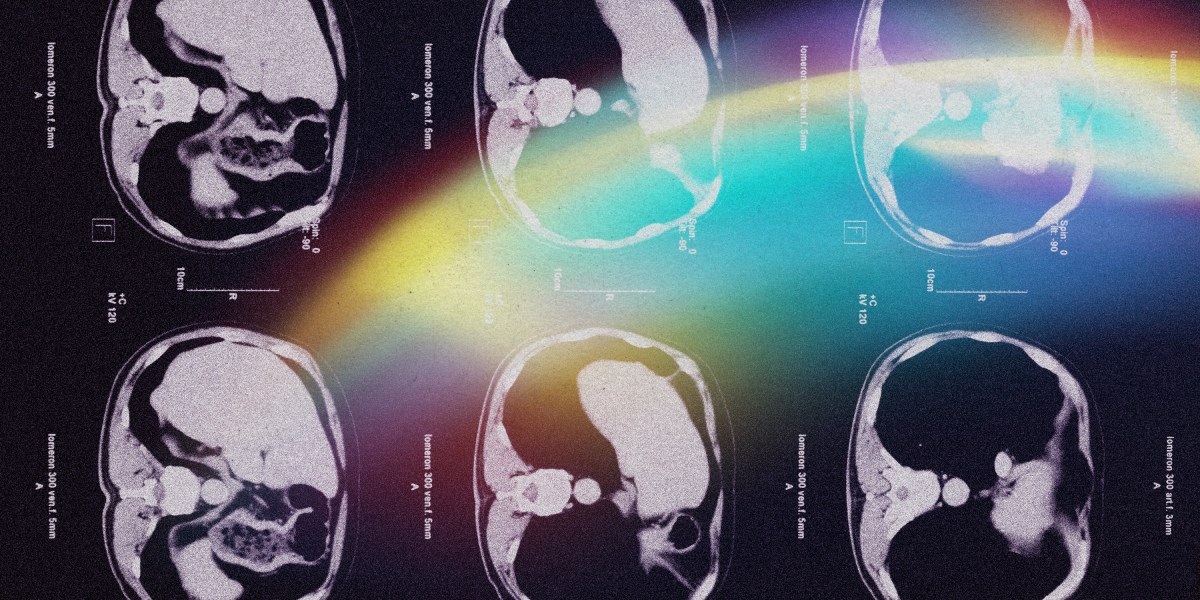

A new AI-based risk prediction system could help catch deadly pancreatic cancer cases earlier